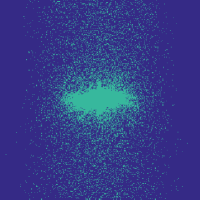

Figure 7 illustrates the best-performing randomized indices vs. our learned set of indices in the -space along the and directions. When optimized for the linear decoder, the indices of [3, 4] concentrate on low frequencies. While our strategies based on optimizing and (again using ) also do this to some extent, there is a stark contrast in the shape, since we do not restrict ourselves to patterns exhibiting circular symmetry.

Table III illustrates the overall test performance of each approach, in addition to the error obtained by the best adaptive (i.e., image dependent) -sample approximations with respect to the -space basis. Based on these numbers, the learning-based approach slightly outperforms the randomized variable-density based approach of Roman et al. [4], which in turn slightly outperforms that of Lustig et al. [3]. The best PSNR in each case is achieved by the indices corresponding to ; with this choice, even the linear decoder leads to an improvement over [3] and [4] used with BP, while using our indices alongside BP provides a further improvement. Finally, based on Figure 8, it appears that the improvement of our indices is actually more significant in the relevant parts of the image where the knee is observed, with finer details being seen at and sampling rates.